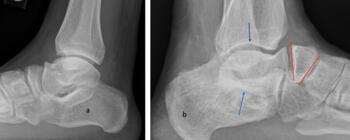

One of the most disturbing complications with any casting is the development of flat top talus. Overly aggressive attempts to dorsiflex the ankle often lead to met primus elevatus, but the flat top talus ruins the ankle joint during development. When I work with residents and students, I always stress the importance of avoiding dorsiflexion completely during the casting phase simply because I do not want to create a deformation of the talus. I reserve all of my sagittal plane correction for the Achilles lengthening and posterior capsule release. Unfortunately, I see more and more cases of flat top talus as a result of the Ponseti method. Khan and colleagues in 2021 reported a significant increase in their study and review of the literature, blaming it solely on overly aggressive casting and manipulation.16

So, to summarize, true congenital clubfeet have abnormal talar bodies, which lead to abnormal ankle and subtalar joints with short Achilles and tight posterior tibial tendons. Regardless of treatment, there is nothing anyone can do to make the talus a normal bone. Many of these cases can and will develop additional deformities. Only the Cincinnati release can address every issue associated with the deformity, but it is NOT a cure. The Ponseti procedure is a total compromise, also NOT a cure. The sooner everyone treats the Ponseti as a compromise, I believe we will be far happier with the outcomes. I remember discussing this with others treating pediatric orthopedic issues during the rise of the Ponseti in the early 2000s. We all agreed, undercorrecting the deformity will lead to more surgeries and residual deformities. Until we all face the reality that clubfeet are a genetic deformity and not just a positional deformity, we will never make them perfect. Thus, athletes and the military will put any and all clubfeet patients to the test. There is no doubt that exceptions exist, but in time, at least based on our limited review of over 1000 clubfeet and 250 cases we saw in the military, no one is immune to complications, arthritis, and ultimately disability.

Here is a typical case presentation. A 21-year-old Marine at Ft. Leonard Wood for training underwent a Cincinnati release at one year old and had stellar follow-up. Her surgeon even wrote her medical waiver for entrance into the Marines. She ran track in high school. She finished boot camp and completed all of her Marine training, but now has chronic pain. She no longer can run. She hasn’t passed her physical training in over a year. She developed talonavicular DJD. By all accounts, her overall clubfoot should be rated an A+; no residual deformity, normal talocalcaneal angles on AP and lateral views, no equinus, no residual varus, only slight met primus elevatus, but no signs of a flattop talus. Clinically, she lacks subtalar range of motion, which I commonly find post-clubfoot release of any kind. So many in the military do very well for a while, but the demands of the military eventually catch up to them. We all root for clubfeet to make it, but the odds are stacked against them.